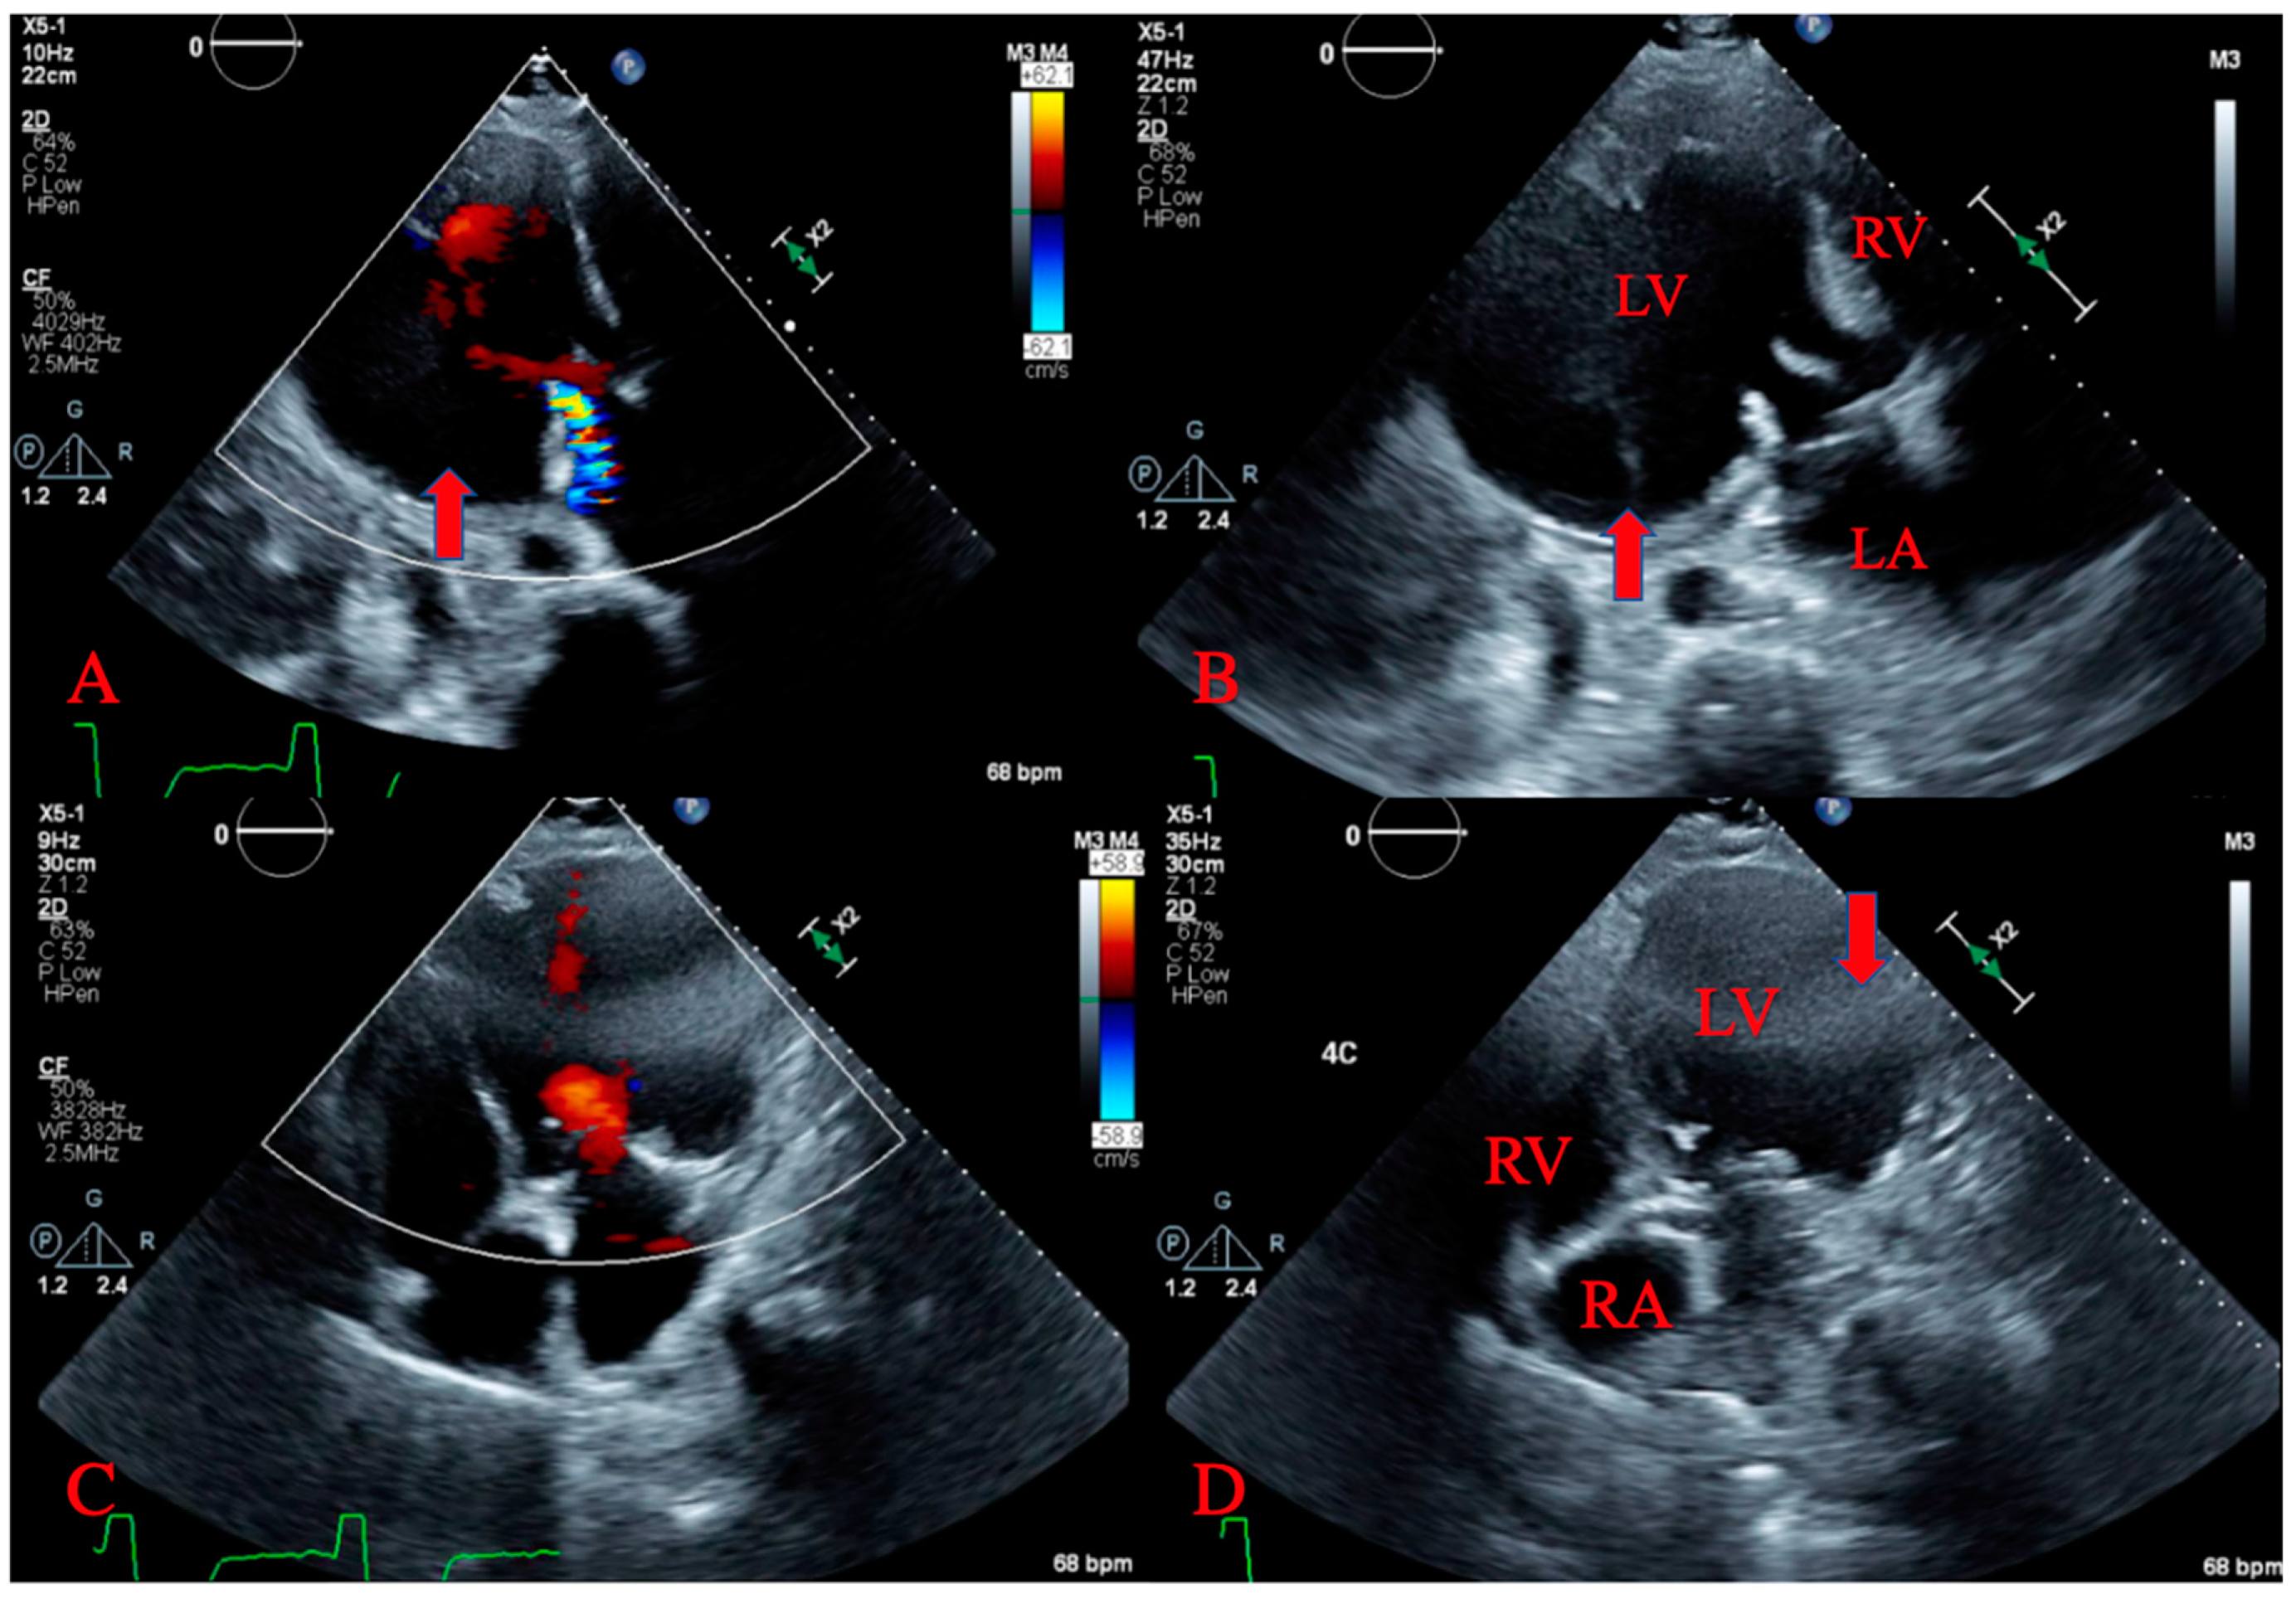

2. Case Presentation